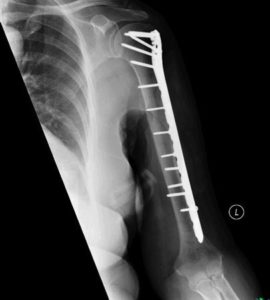

Focus on Fractures HW CPT Review for students RTD

NCCI Musculoskeletal